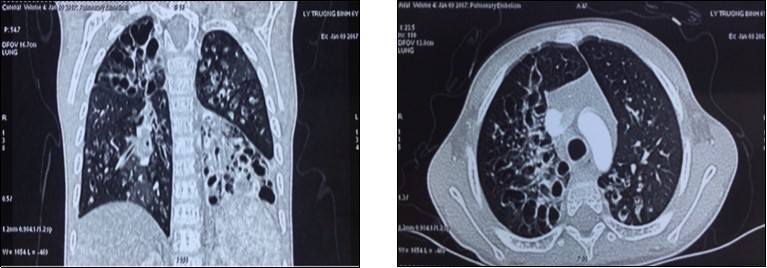

Early outcome: After the operation, the patient was ventilated via endotrachial tube, controlled the status of respiration, hemodynamics and draignage care. Recipient was weaned off ventilator in 36 hours. Postoperative immunosuppression consists of triple drug therapy with neoral, cellcep, and prednisolone. We judge acute rejection on the clinical, radiographic fndings, other subclinical tests and control opportunistic infection. At 1, 3, 6, 9 and 12 months after LDLT, the recipient has recovered lung function very fast and there were not any early complications and adverse events after the operation. Now the recipient had normal physical exercise capacity, subclinical tests in normal limits and not respiratory symptoms, opportunistic infection and no evidence of rejection. (Image 2)

Image 2.The chest X-ray images at the first (a), 7th day (b) and 12th month (c). CT-scan images at the 3th day (d) and 8th day (e) after lung transplantation.

The chest X-ray images at the first (a), 7th day (b) and 12th month (c). CT-scan images at the 3th day (d) and 8th day (e) after lung transplantation.

In recent years, the number of lung transplantation patients has increased remarkbly with the trend to bilateral lung transplantation more than single lung transplantation. The sources of donors are extended, with non-heart beating donors, ex-vivo lung perfusion and living donors. LDLT is a last option chosen to save critically ill patient with end-stage pulmonary disease who cannot wait for organs from cadaveric donor4. In our receipient, the indication of lung transplantation was resonable because he always had recurent respiratory infection, decreased PaO2, increased oxygen requirements, hypercapnia, pulmonary arterial hypertension. Two donors were relative and young. The anatomic and functional size matchings between the receipient and two donors played a very important role in the success of this lung transplantation case. We use a formula to estimate graft FVC (Forced vital capacity) on the basis of the donor’s measured FVC and the number of pulmonary segments being implanted4. The right lower lobe FVC of uncle estimated 0.71 (L), the left lower lobe FVC of father estimated 0.8 (L), the receipient FVC estimated 0.98 (L). Total FVC of the two grafs/ FVC of the recipient was 1.5 (according to the Japanese authors, it is acceptable when this ratio > 0.45). Therefore, after vetilation these 2 lung lobes expanded nearly completly with the size of the paient’s chest cavity and by the 7th day, both 2 lung lobes had expanded completly. At the 1st, 3th, 6th , 9th and 12th month, the chest X-ray image are normal. The clinical change of the recipient: fever immediately after operation and recovered in 2 days, sputum in 5 days, oxygen therapy in 5 days; weaned off ventilator in 36 hours. After 4 days, he was withdrawn from thoracic drainage and could walk himself in the room at the 6th day after the operation. In the 1st, 3th, 6th, 9th and 12th month, he had normal physical activities, not any clinical symptoms (now he returns to school and takes part in all activities as his classmates), subclinical tests in normal limits and no evidence of opportunistic infection or rejection.